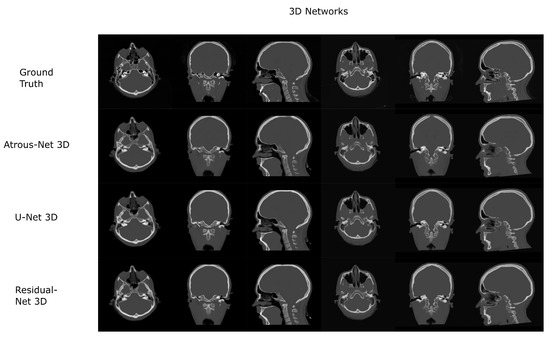

3.2. Pelvis Dataset Results

The results for all tissues using the pelvis dataset are depicted in Table 16, Table 17 and Table 18; the results using only the bone voxels are detailed in Table 19, Table 20 and Table 21; the results using only the fat voxels are detailed in Table 22, Table 23 and Table 24; and the results using only the soft-tissue voxels are detailed in Table 25, Table 26 and Table 27. In the pelvis dataset all networks performed very similar when all tissues were considered. However, 3D networks obtained slightly worse results when assessing bone alone and very similar results for all tissues. The best network in the bone dataset was the 2D Residual network that obtained a MAE of 201.56 HU, a PSNR of 23.20 and a Pearson Coefficient of 0.476 in the bone. Additionally, the error in bone with all networks increased when the 3D scheme was used. The ANOVA test for the 2D results reported a statistically significant effect of the networks in all tissues and bone MAE (all tissues: F 2 , 56 = 6.7 , p < 0.005 ; bone: F 2 , 56 = 8.5 , p < 0.001 ) and PSNR (all tissues: F 2 , 56 = 8.5 , p < 0.001 , bone: F 2 , 56 = 5.3 , p < 0.01 ). According to 3D results, the ANOVA test did not expose statistically significant differences when using different architectures on all tissue MAE (all tissues: F 2 , 56 = 2.3 , p = 0.10 ; bone: F 2 , 56 = 6.2 , p < 0.005 ) and PSNR (all tissues: F 2 , 56 = 1.4 , p = 0.25 ; bone: F 2 , 56 = 4.3 , p < 0.05 ). Post hoc Student’s t-test is depicted in Table 28 and Table 29. It reveals that the Residual-net and Atrous-net did not provide statistically significant differences. Visual result examples of pelvis pseudo-CTs are depicted in Figure 8 and Figure 9. Table 30 shows the time needed to synthesize a whole pelvis volume using the different architectures.

Figure 8. Pelvis results using 2D networks.